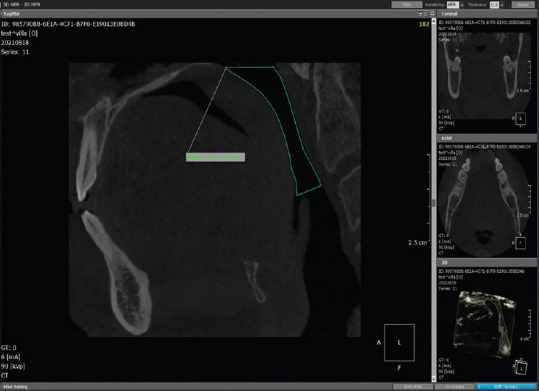

Materials and methods: In this cross-sectional observational study, 300 cone-beam computed tomography (CBCT) scans were examined and coded matching the subjects in the experiment for age and gender. OnDemand three-dimensional (3D) software was used to generate 3D models for the airways of the subjects and for calculating their airway volumes.

Abstract Image